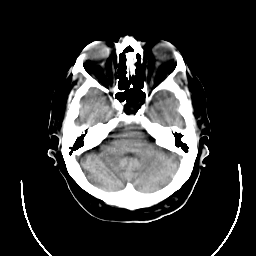

CT Study #3 -- Slice #7

[Home][Help][Clinical][Tour 1] Slice 7